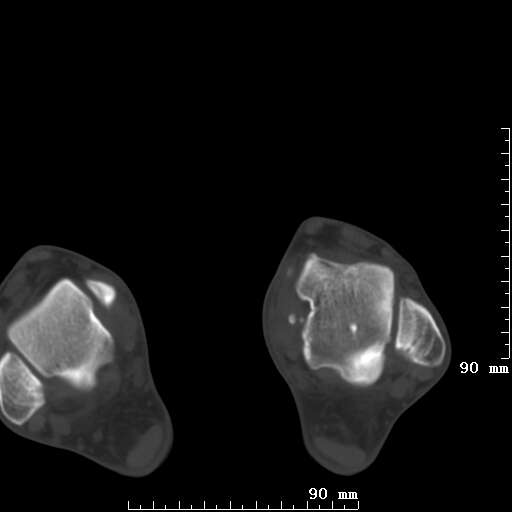

标题: CT19820:外伤一天,如何定性.男27Y [打印本页]

标题: CT19820:外伤一天,如何定性.男27Y

排除下创伤性关节炎吧,距骨有些囊变和硬化,周围韧带软组织有些机化、钙化。不是很像距骨无菌性坏死,感觉在关节面上的多,而不是距骨里面。

未见骨折及脱位像。距骨像是剥脱性软骨炎

支持!(踝关节距骨表面囊变和硬化 缺损)

距骨剥脱性软骨炎可能;踝关节创伤性关节炎?

未见明确新鲜骨折改变,距骨剥脱性软骨炎或踝关节创伤性关节炎可能。

关节周围多发高密度影,要结合病史